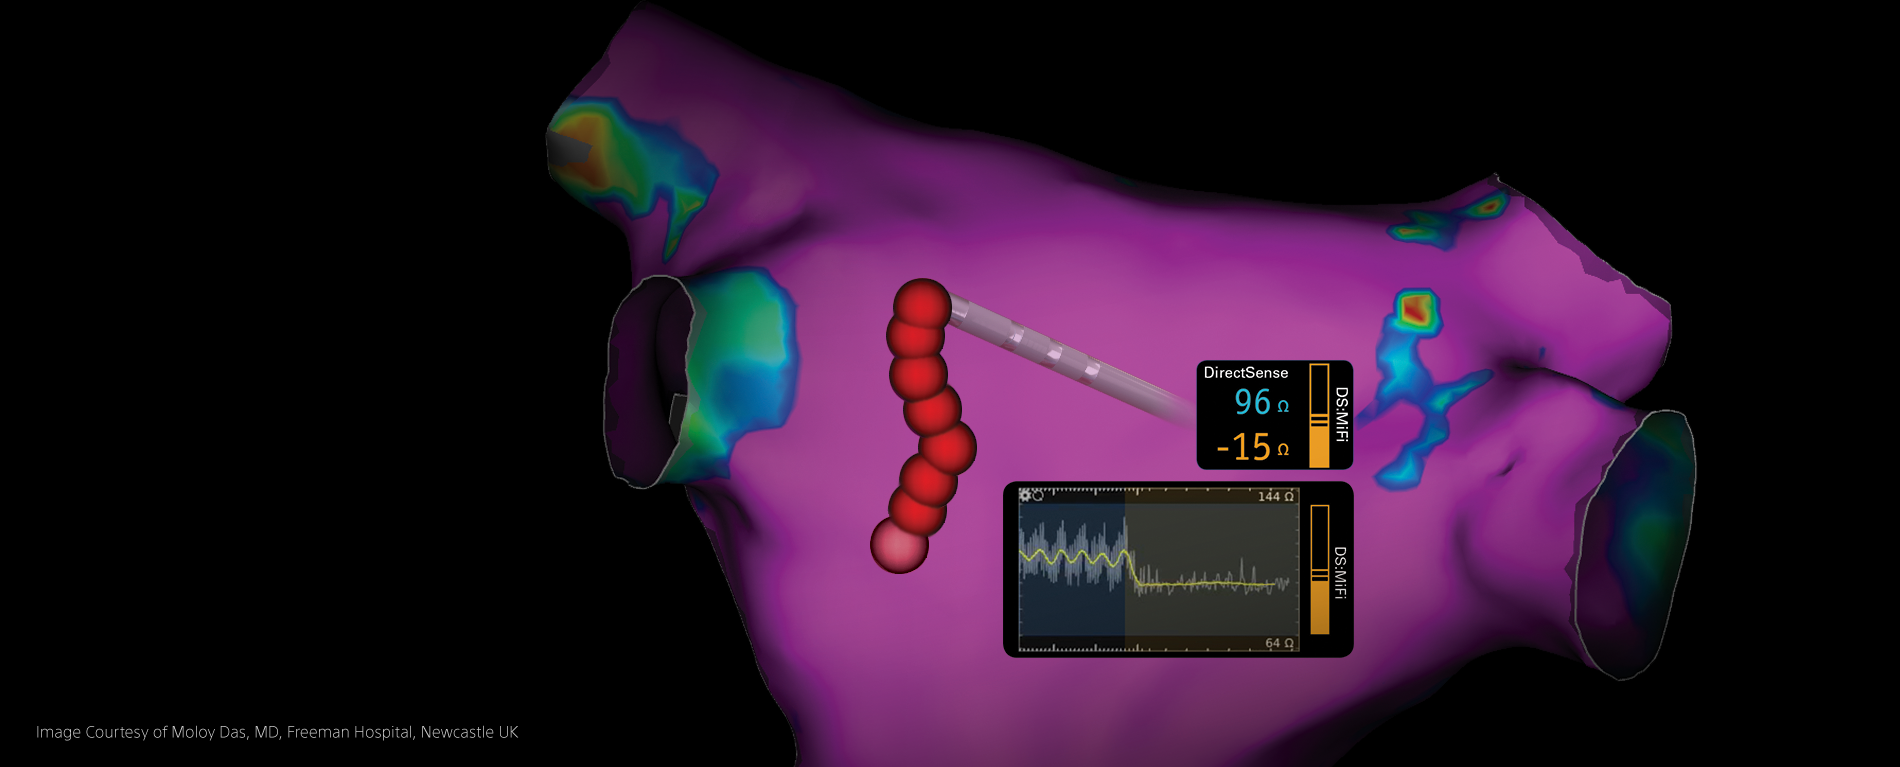

DIRECTSENSE™ Technology Clinical Data

Explore pre-clinical and clinical data supporting the benefits of having localized tissue insights and critical feedback during radiofrequency (RF) ablation procedures.

Novel Measure of Local Impedance Predicts Catheter-Tissue Contact and Lesion Formation

Circ Arrhythm Electrophysiol, Sulkin, et al., April 2018